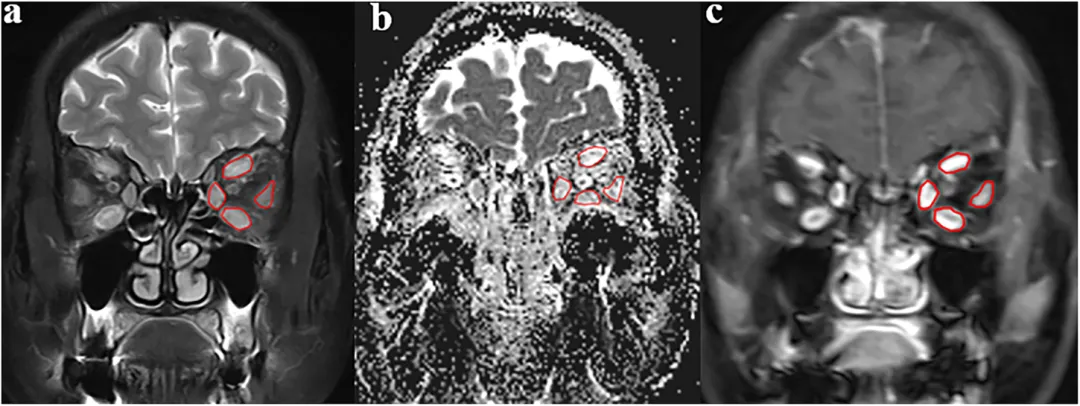

图2:影像分析示意图。展示眼外肌ROI勾画及参数提取过程。

图3:活动与非活动TAO患者的代表性影像图例。